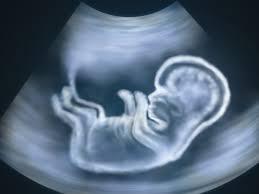

The news of a baby’s arrival is always very much exciting to couples. Would-be parents cannot keep calm as they are going to hold another little hand for the rest of their lives. In such situations, many couples can hardly wait to know the gender of their babies and they visit gender scan clinics in Milton Keynes to know their baby’s gender. Contrarily, many couples are also there who do not feel it necessary to undergo a baby scan to know their baby’s gender. Taking both these points of view into consideration, we thought it helpful to draw a list of pros and cons of gender scanning in this article.

Knowing your baby’s gender beforehand is an action that might influence the second half of your pregnancy, but cannot influence your baby’s gender. On the other side, many would-be parents prefer not to reveal it due to the surprise factor and the enjoyment of expectancy. Whatever group you belong to, you must enjoy the entire nine months of your pregnancy. This is because, all a couple wishes for is to have a healthy baby, whether it is a boy or a girl. For that, every expecting parent must visit a 4D baby scan clinic in Milton Keynes to track the unborn baby’s growth and development.